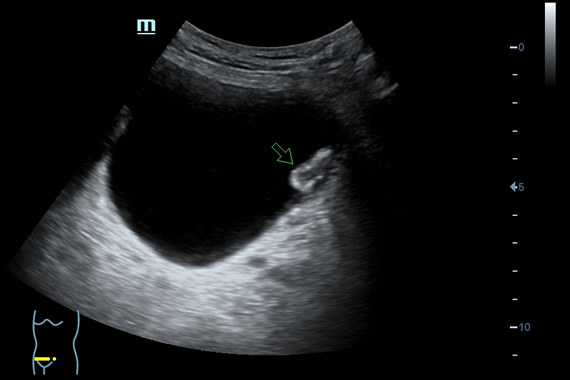

Система ультразвукового исследования Mindray DC-60 EXP X-INSIGHT является новейшей разработкой для проведения комплексных обследований на высшем уровне. Она обеспечивает решение самых сложных задач в таких областях, как кардиология, акушерство и гинекология, сосудистые заболевания, педиатрия и многие другие.

DC-60 EXP X-INSIGHT - это современный стационарный УЗИ-аппарат с функцией сенсорного управления и очищенной гармонической визуализацией, обеспечивающей лучшее контрастное разрешение и технологию 4D-визуализации. Он оснащен 21,5-дюймовым монитором, который может поворачиваться на 180 градусов, что удовлетворяет потребности врачей в качественной ультразвуковой диагностике.

Одним из ключевых преимуществ DC-60 EXP X-INSIGHT является технология формирования УЗ-луча. Она дополняет основной луч параллельно эхо-сигналами, что приводит к получению более мощного сигнала и изображений высокого качества с помощью систем iLive, iPage, Smart OB, Smart NT.